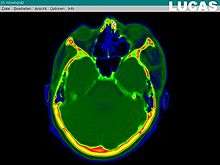

Image analysis involves the manipulation of the patients 3D model to extract relevant information from the data. Using the differing contrast levels of the different tissues within the imagery, as examples, a model can be changed to show just hard structures such as bone, or view the flow of arteries and veins through the brain.